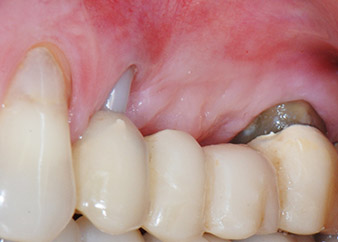

One month later, on the day of surgery, pain and inflammation at tooth 24 were minimal, but mobility of Miller class 2 was still present. After opening the flaps and cleaning the periapical and peri radicular infected tissue, the extent of the bone defect became obvious (Figs. 2 and 3).

At the buccal root, all vestibular and distal bone was missing. Attachment was essentially restricted to the palatal root, underlining the preliminary poor prognosis. Tooth 27 also showed a reduced horizontal attachment and a minimal apical rarefaction (cf. Fig. 1) without clinical symptoms.

However, we maintained our initial plan to retain both teeth as temporary bridge abutments during the six-months osseointegration period of the implants. At reentry, the situation would have to be reassessed. First, in an attempt to manage the endo-perio problem, the remaining root surface was carefully debrided with piezoelectric equipment (Piezomed, W&H, used with the spatula-shaped insert S1, originally designed for erosion of the lateral sinus wall) (Fig. 4).